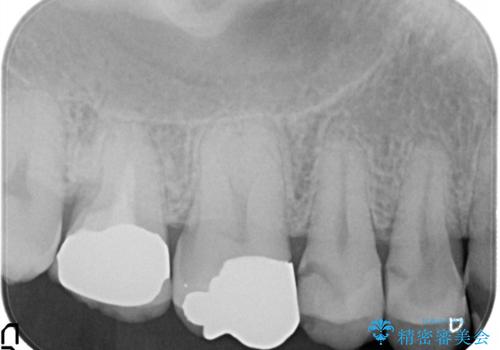

- 定期検診にて不良補綴物、及び虫歯を認めオールセラミッククラウンにて治療を行いました。

右上第二小臼歯はカリエス除去中に露髄を認め、部分的断髄法にて歯髄を保存しております。